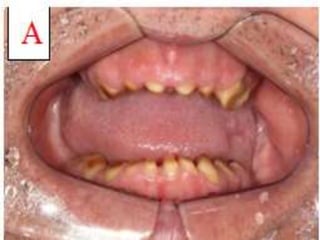

• Oral Manifestations: White spots / patches / or areas of

localized inflammation may precede the development of

bullae

• The bullae may be initiated by even a simple dental

operative procedure and large areas of denudation of oral

mucous membrane can occur without proper precautions

• Bullae are painful and scarring results in obliteration of

vestibule, or restriction of tongue

• Hoarseness or dyaphagia may occur as a result of bullae of

larynx or pharynx

• Dental Defects: Rudimentary teeth, Congenitally absent

teeth, Hypoplastic teeth, Absence of enamel on crowns